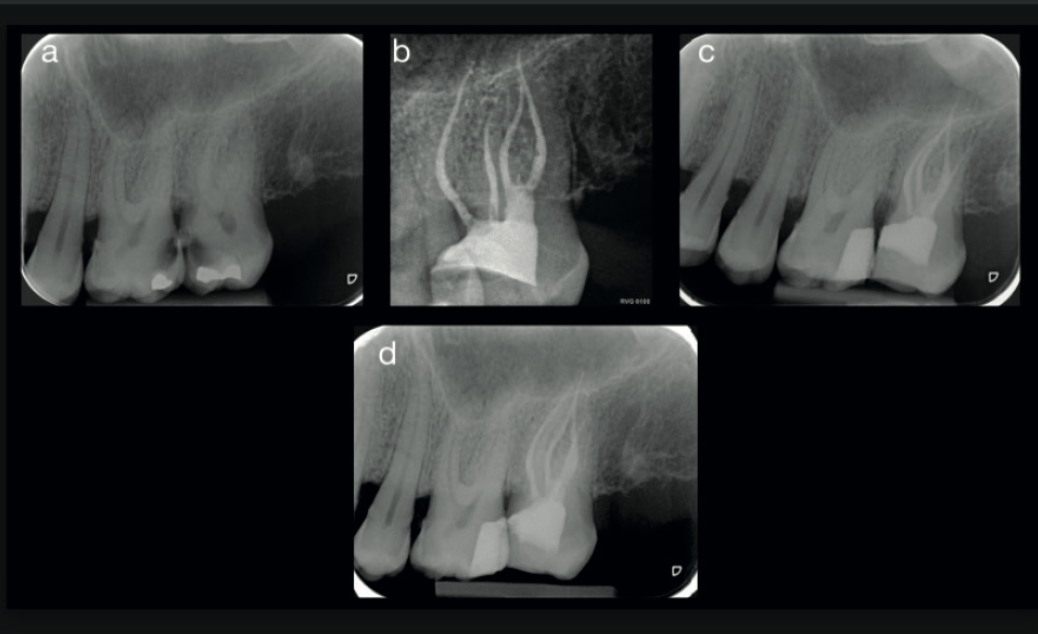

Fig. 2 — Root canal tracing tool applied to the buccal roots of UL7 Fig. 3 — Root canal tracing tool showing two canals in the palatal root of UL7

Fig. 2 & 3 The 3D imaging software's root canal tracing tool mapped the full canal system before treatment began — buccal roots (left) and the two palatal canals (right).

Virtual treatment planning was then carried out using 3D imaging software with a root canal tracing tool. This allowed the clinician to map the entire canal system before touching the tooth — assessing morphology, planning the access cavity, and reducing the risk of perforation, missed canals, or instrument separation.